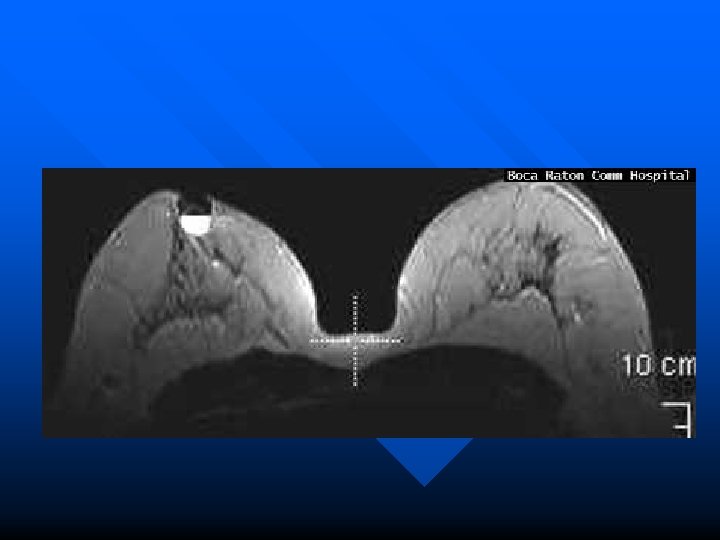

Example Case n n This 61 year old female presented with a dominant mass in the right breast with several other indeterminate lesions seen on mammography. Mammography CC view demonstrates three masses in the right breast, one behind the nipple and two others in its medial portion.

n MRI magnification maximum intensity projection (MIP) view of right breast demonstrates the same three masses with tumor bridging between them and extending toward the chest wall.

n MRI T 2 axial slice indicates cystic nature of subareolar mass.

n MRI subtraction and color images show rim enhancement around cystic mass.

n MRI image of color map of enhancement curves (kinetics of breast tissue) show intense early enhancement and rapid signal loss from the dominant mass (typical malignant characteristics).

n n n Enhancement curve from dominant mass. Final Pathology at mastectomy confirmed that the dominant mass represented infiltrating carcinoma with extension of intraductal carcinoma. The subareolar cystic mass represented encysted papillary carcinoma.